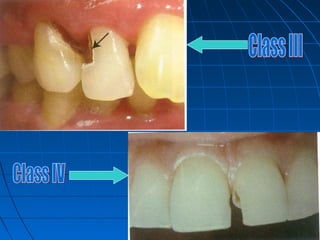

Dental caries is an irreversible microbial disease that causes demineralization and destruction of tooth structure, often leading to cavitation. It is classified based on anatomical site as occusal, smooth surface, or root caries. Inter proximal caries specifically refers to caries between teeth, which can be detected via bite-wing x-rays for low or moderate risk patients. Proper dental care and hygiene is important to prevent recurrent caries.